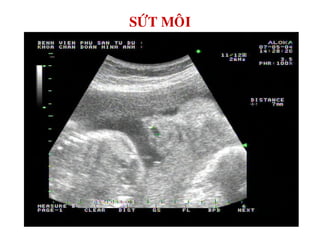

SÖÙT MOÂI

MOÂI TREÂN HÔÛ

SÖÙT MOÂI TREÂN 3D